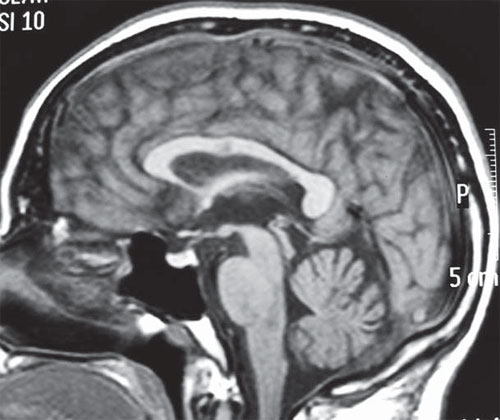

Fenitoína: los niveles séricos elevados pueden producir atrofia cerebelosa

02 agosto 2016

EMC, 1º de agosto de 2016